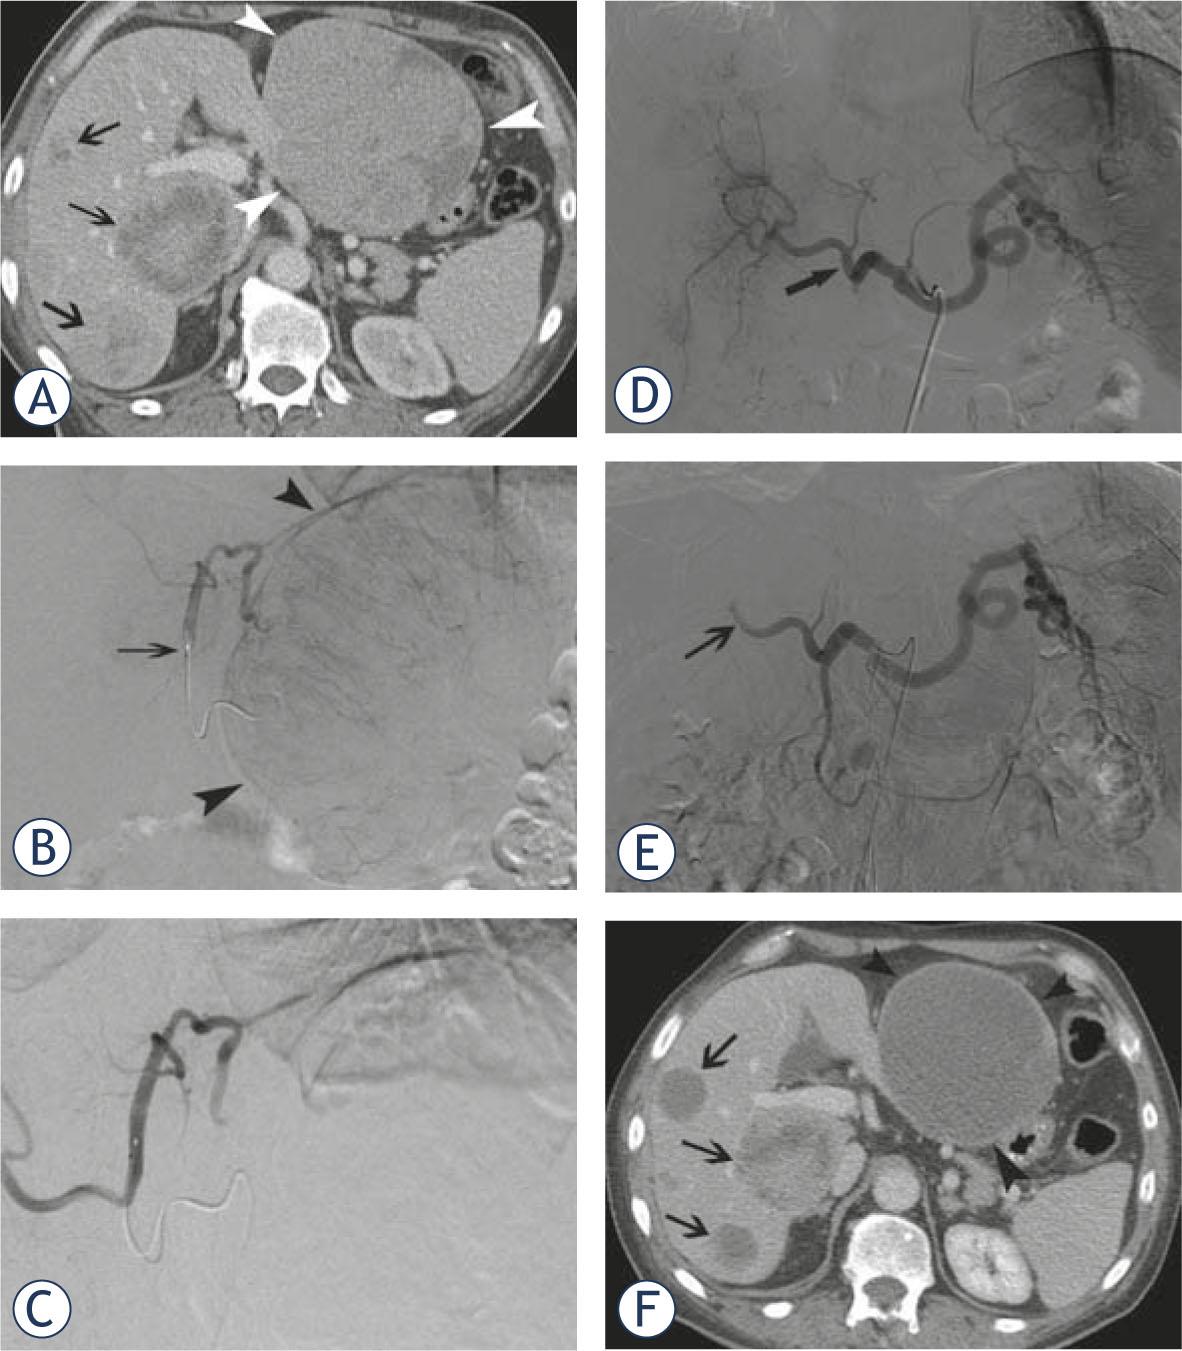

A 63-year-old male patient presented with a carcinoid of the lung and diffuse bilobar liver involvement. (A) Portal venous phase contrast-enhanced CT-scan confirms diffuse metastatic involvement of both liver lobes (white arrowheads at the level of the largest metastasis in the left liver lobe; black arrows at the level of multiple smaller lesions in the right liver lobe); Selective angiogram of the left hepatic artery (B) before and (C) after chemoembolization with doxorubicin-eluting SAP-microspheres (arrow at the level of the micro-catheter in the left hepatic artery); Selective angiogram of the celiac trunk (D) before and (E) after chemoembolization with doxorubicin-eluting SAP-microspheres (arrow shows stasis of contrast at the level of the right hepatic artery); (F) Portal venous phase contrast-enhanced CT-scan 10 weeks after initial chemoembolization shows marked decrease in volume and enhancement of most of the metastatic lesions in left and right liver lobes.

In 5 patients (29%), chemoembolization of right and left liver lobes was performed in separate sessions. Both right and left liver lobes were treated in 8 patients (47%) during the same session (Figure 1). For the remaining 4 patients (24%), isolated right hepatic lobe chemoembolization was performed.